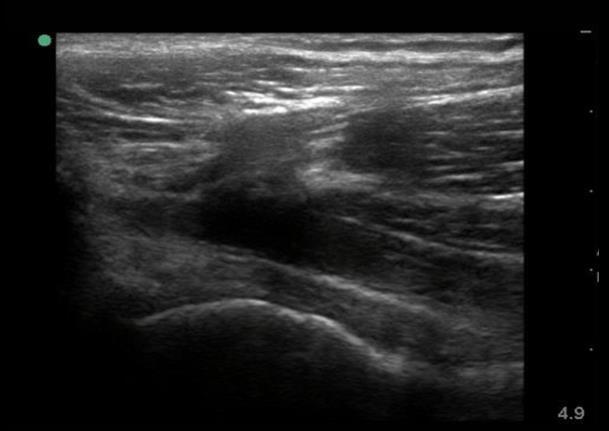

Hip Anterior Joint Recess-Linear Image